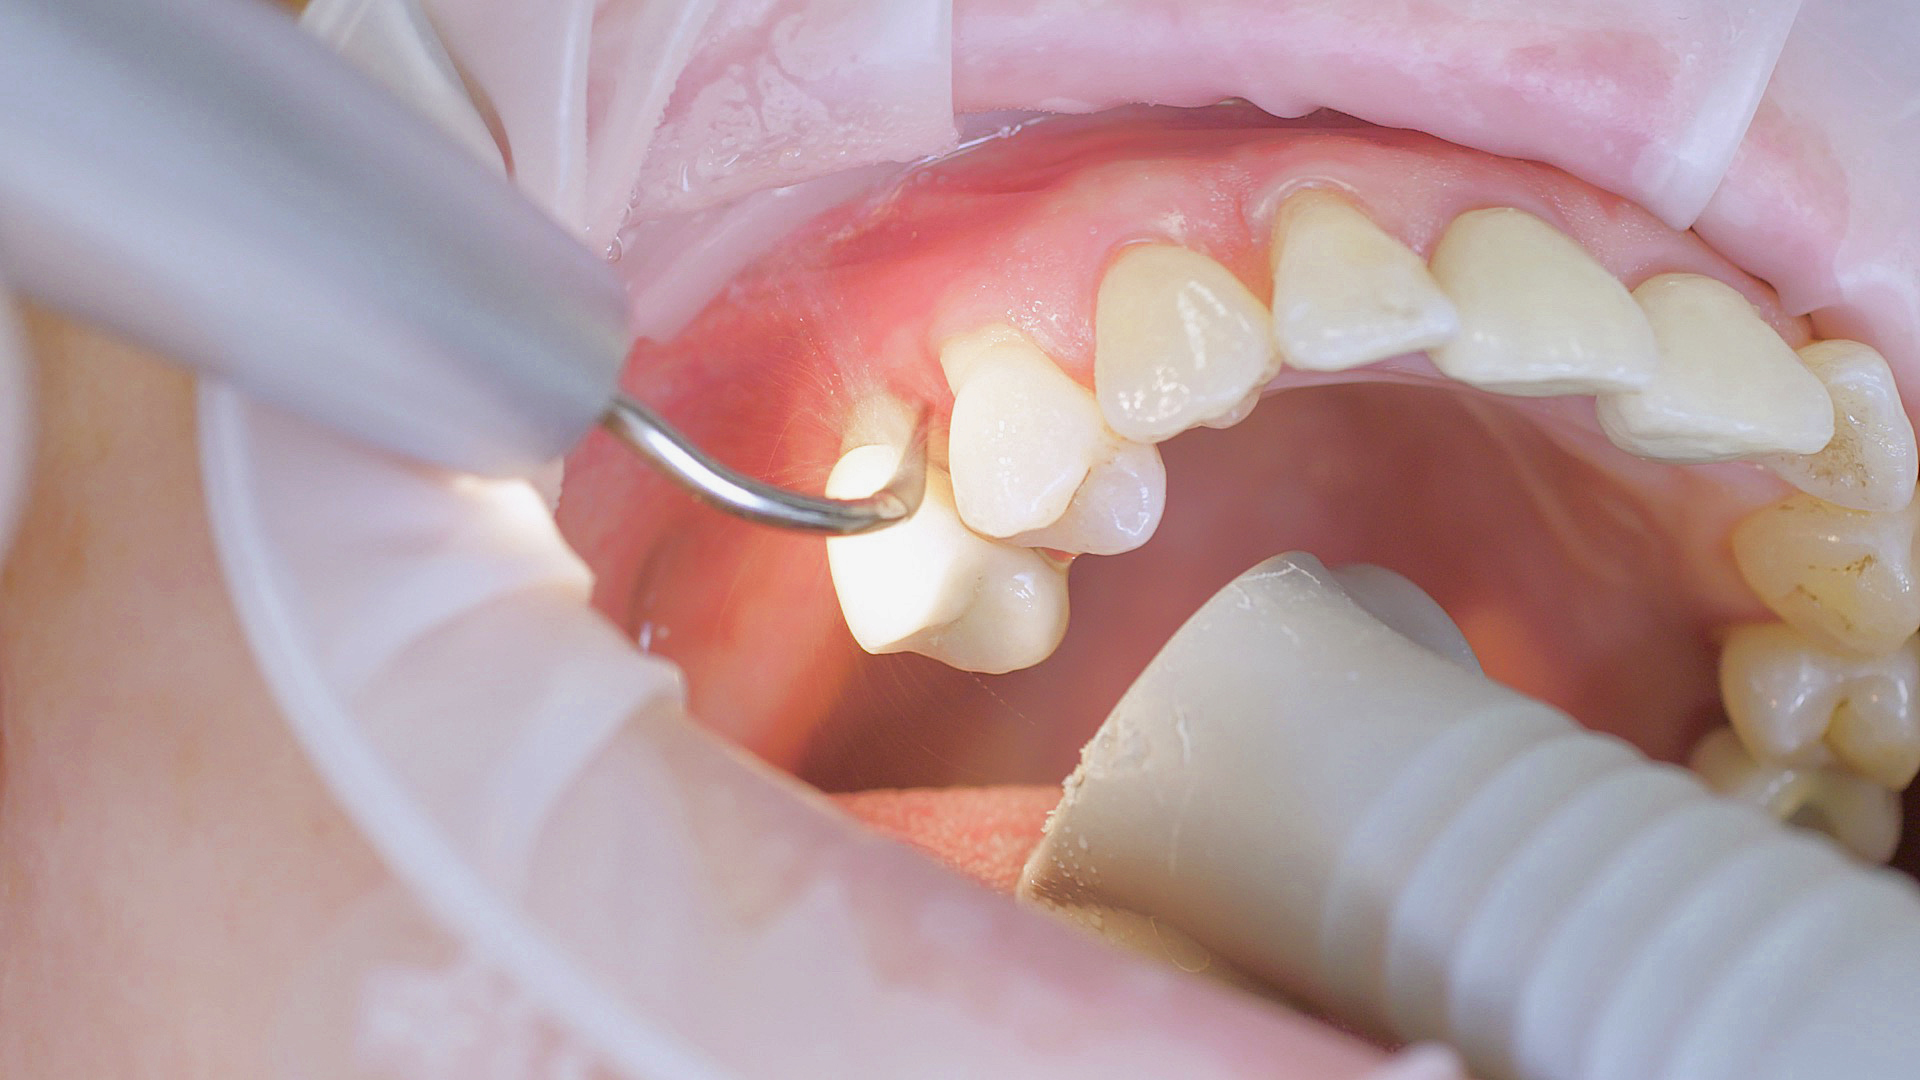

In the periodontal aftercare subsequent to implantation, soft (biofilm) and hard coatings are regularly professionally and mechanically removed.[16, 17] In the subgingival and supragingival areas, ultrasonic devices are generally used for this (Fig. 4), in combination with manual instruments where necessary. Alternatively, subgingival air polishing can be used in combination with periodontal attachments and powders.[18]

At-home oral hygiene should be carefully tailored to the new prosthesis and the patient accordingly instructed on this.[34] In combination with professional biofilm management, good preventative efficacy can be achieved in this way.[35] The risk of peri-implantitis decreases from 43.9 per cent (no recall) to 18.0 per cent if a patient receives a recall appointment carried out carefully each year, in other words by more than half.[36] Ultrasonic systems with special instruments that do not affect the materials are suitable for this, such as those made of PEEK (Fig. 5), or appropriate manual instruments.[37]